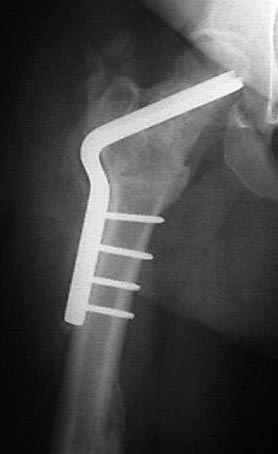

Несколько снимков из моей коллекции, чтобы разьяснить, почему мы до сих пор делаем различные варианты остеотомии.

На рисунке N1 предоперационный план лечения ложного сустава шейки бедра- линия ложного сустава, угол и направление введения импланта, клиновидная остеотомия в градусах и миллиметрах, второй снимок после коррекции, расчет, на сколько удлиняется конечность и размеры импланта;

N3 рисунок окончательный снимок, после операции моя рентгенограмма должен выглядеть примерно как эта картина. На N4 снимке клин перед удалением; N5 послеоперации 3 нед.; N6 окончательная рентгенограмма.

варус при проксимальном отделе 95 градусной пластиной.